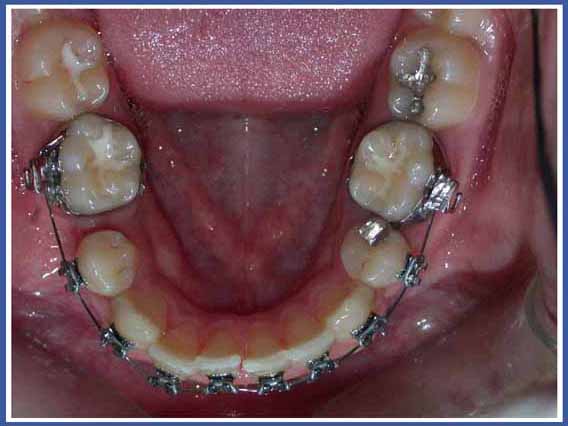

סמכים אורתודונטים (גשר) Brackets:

האמצעי הנפוץ ביותר כיום להזזת שיניים. הסמכים המודבקים לשיניים והחוט שעובר ביניהם מאפשרים להזיז את השיניים בכל שלושת המימדים בשליטה מלאה על התנועה, בניגוד לפלטות שיכולות להזיז שיניים רק בהטיה (רק לשנות את הזווית של השן בלסת). סמכים יכולים להיות מתכתיים או שקופים.

לסמכים המודבקים לשיניים יש יתרונות רבים אך יש להם גם חסרונות. החסרון העיקרי הוא הצטברות שאריות מזון וחיידקים עליהם. כדי למנוע סכנה לעששת (חורים) מסביב לסמכים, יש להקפיד על צחצוח שיניים קפדני במהלך הטיפול, ולהמנע ככל האפשר ממזון המזרז את התפתחות העששת (מזון עשיר בסוכר).

הנחיות לשמירה על הגיינה בזמן הטיפול האורתודונטי באמצעות סמכים (גשר):

חשוב מאד לנקות בין השיניים והטבעות, שכן לחיידקים יש נטייה גדולה יותר להימצא במקומות אליהם קשה לנו להגיע. פעולה זו תמנע בעיות ועששת גם לאחר סיום הטיפול והורדת הסמכים.